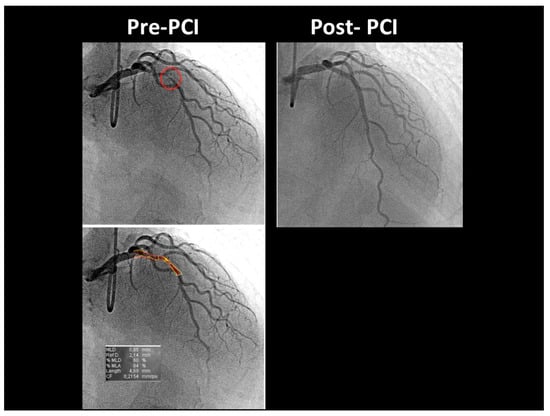

At the COVID intensive care unit, he was admitted to the catheterization laboratory, where he received immediate intravenous therapy, 5000 IU heparin sodium, 250 mg lysine acetylsalicylate and cangrelor bolus followed by continuous infusion (according to body weight). Coronary angiography showed sub-occlusive stenosis (lumen narrowing = 86%) of the proximal LAD (Figure 4), which was treated with balloon angioplasty followed by drug-eluting stent placement (Resolute Onyx 2.75 × 34 mm). Following the intervention, 0% residual stenosis was recorded, with an optimal residual flow and no dissection present (Figure 4). A total of 2 hours post-procedure, 180 mg oral ticagrelor (after the suspension of cangrelor) was administered, followed, from the following day, by 100 mg oral aspirin daily, 90 mg oral ticagrelor bis in die (as part of a dual antiplatelet regimen) and goal-directed medical therapy with a beta-blocker and highly intense statin therapy [19]. The ECG following PCI displayed persistent pseudo-normalization of T waves in the precordial leads; cardiac high-sensitivity troponin T (III assay) increased considerably to 3734 μg/L. Patient recovery was event-free, and he was transferred on the fourth day to the internal medicine department, pending the negativization of the SARS-CoV-2 molecular assay. He was discharged on the 7th day on dual antiplatelet therapy but not on anticoagulation therapy since his COVID infection had no thromboembolic complications [20]. After two months, he was re-evaluated by E-Doppler TTE, this time adding CFR assessment. The transtenotic velocity had dropped almost completely, indicating a patent stent (minimal residual stenosis at 26% of area reduction according to the continuity equation) (Figure 5), and the CFR was also normal (=3.3) (Figure 6), confirming the stent patency and complete recovery of microcirculatory function in the LAD myocardial territory.

Figure 4. Coronary angiography before and after PCI. Before PCI (top left), coronary angiography (CRA 33° RAO 27°) showed a long, significant critical stenosis (red circle) of the proximal LAD; the (bottom left) image shows the QCA of the same pre-PCI image, demonstrating an 86% area reduction; after PCI, coronary angiography (top right) (CRA 35° RAO 14°) shows the optimal final result, with no residual stenosis. PCI = percutaneous transluminal coronary angiography; QCA = quantitative coronary angiography; CRA = cranial; RAO = right anterior oblique view; PCI = percutaneous coronary intervention.